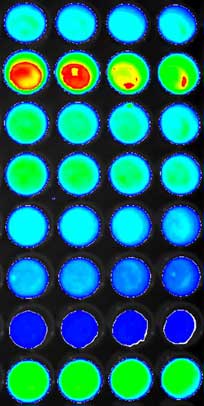

in vitro assays allow rapid screening of numerous chemicals in 96 or 384 wells plates such as hormone analogs and are therefore widely used to detect them in human or environmental samples.

in vivo action can be confirmed in immunodeficient mice in close collaboration with the IPABS platform. After cells xenografting into athymic nude or Scid mice, several ligands for the nuclear receptors can be tested, and different administration protocols can be used in term of dose-response, way of administration and specificity to the compound. Non-invasive monitoring and imaging of tumor cells, through their luciferase gene constitutive expression, are performed in living preclinical model using a CCD camera.

The preclinical model can be imaged daily and allow us to detect the hormonal response after the injections by the chemical products.

Quantitative analysis allows us to compare in vitro and

in vivo actions of different compounds in the same cell lines and to follow hormone action on a living preclinical model as a function of time.